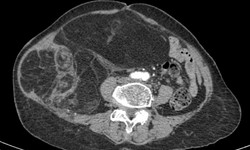

Y tế - 15/08/2025 12:03SKĐS - Sáng 15/8, thông tin từ Bệnh viện Ung bướu Hà Nội cho biết, các bác sĩ của bệnh viện vừa thực hiện thành công ca phẫu thuật loại bỏ khối u thận trái kích thước lớn kèm huyết khối xâm lấn tĩnh mạch chủ dưới cho bệnh nhân nữ 68 tuổi.